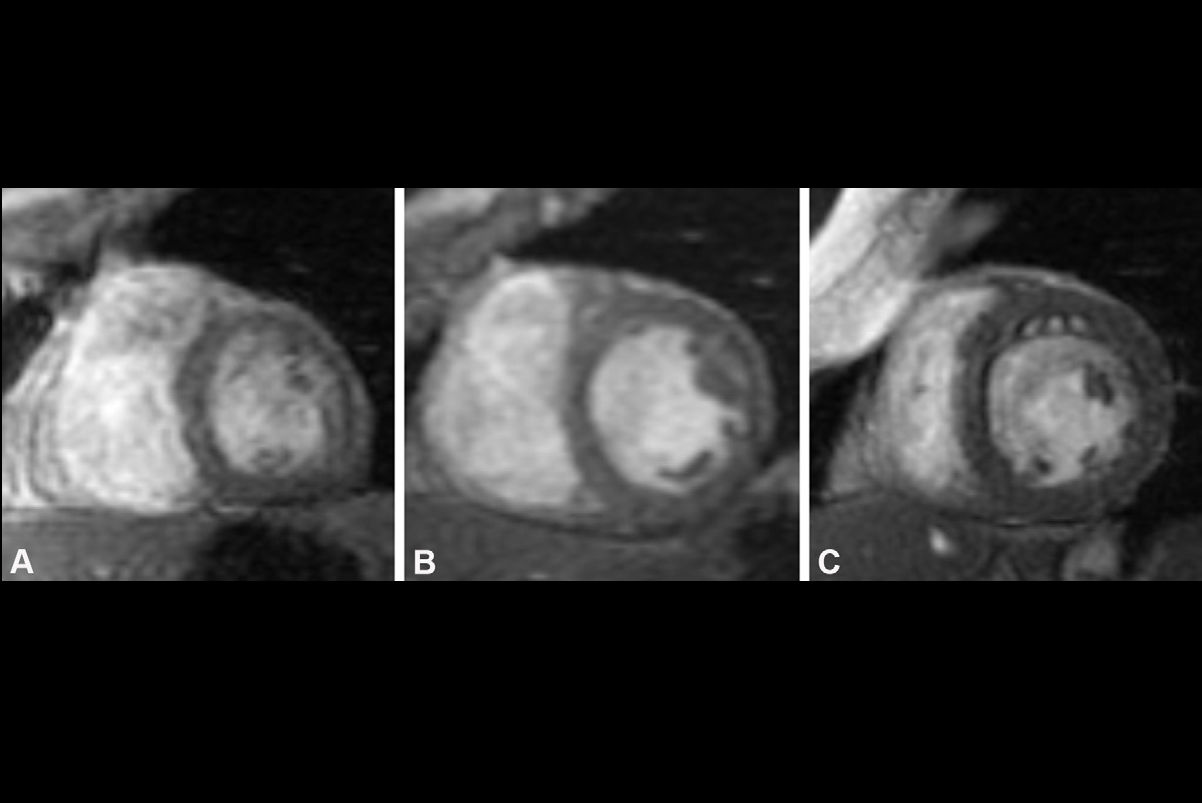

Cardiac MRI cine images in the (A, B) four-chamber (4ch) and (C, D) two-chamber (2ch) views illustrate contouring (red and blue areas) for measurement of left atrial (LA) minimum volume index (LAVImin) at end diastole in two representative participants with acute myocardial infarction (AMI). The LA appendage and pulmonary veins were not considered part of the LA volume. (A, C) Images in a 76-year-old man with a history of coronary artery disease who underwent contrast-enhanced cardiac MRI 4 days after AMI and experienced a major adverse cardiovascular event (MACE), in this case death, during follow-up. LAVImin was 31.84 mL/m2 in this participant. (B, D) Images in a 38-year-old man with a history of angina who underwent contrast-enhanced cardiac MRI 4 days after AMI and did not experience MACE during follow-up. LAVImin was 13.92 mL/m2 in this participant.Caption and image courtesy of RSNA.